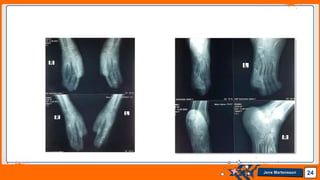

• Radiographs of both feet showed soft tissue syndactyly of all the

toes with synostosis involving metatarsals. Phalanges of great toe

were deformed.